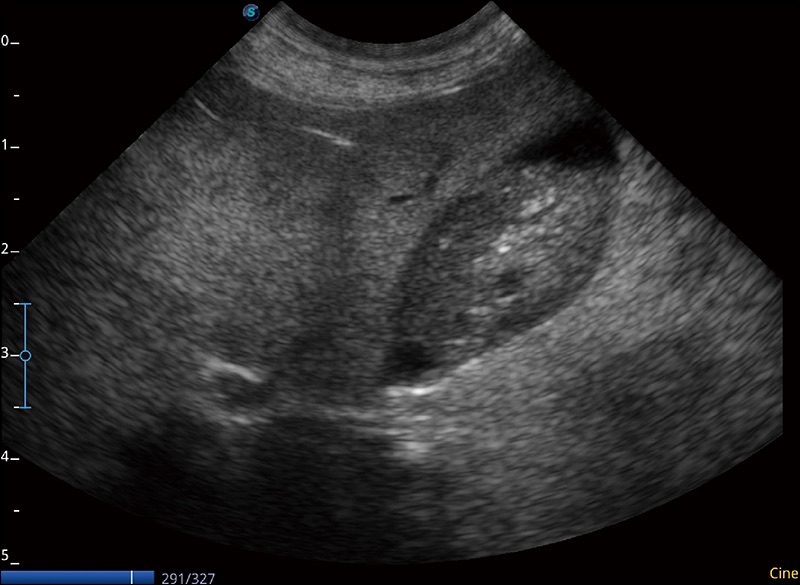

α1卓越的圖像質(zhì)量和便捷的工作流程,使每位寵物醫(yī)生都能輕松掃查。其全面的獸用應(yīng)用功能和緊湊型的結(jié)構(gòu)設(shè)計(jì),可以滿足動(dòng)物檢查的多種需要。專(zhuān)業(yè)的預(yù)設(shè)檢查模式和多領(lǐng)域測(cè)量軟件包有助于為不同類(lèi)型的動(dòng)物提供檢查, 讓寵物醫(yī)生能夠出色的完成工作。